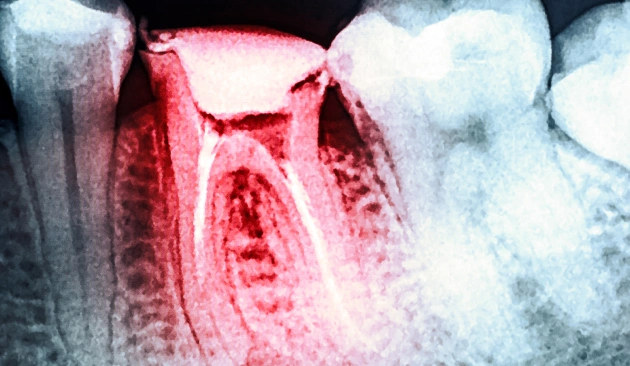

What Is a Root Canal and How Does Tooth Infection Develop?

A root canal is the natural, hollow space inside a tooth that houses nerves and blood vessels. When decay becomes deep, a tooth cracks, or repeated dental work weakens the tooth, bacteria can reach the pulp and cause infection.

Once the pulp is infected, the only way to save the tooth is by removing the damaged tissue and cleaning the canals. Ignoring the infection can lead to severe pain, swelling, bone loss, or even the spread of infection to other areas.